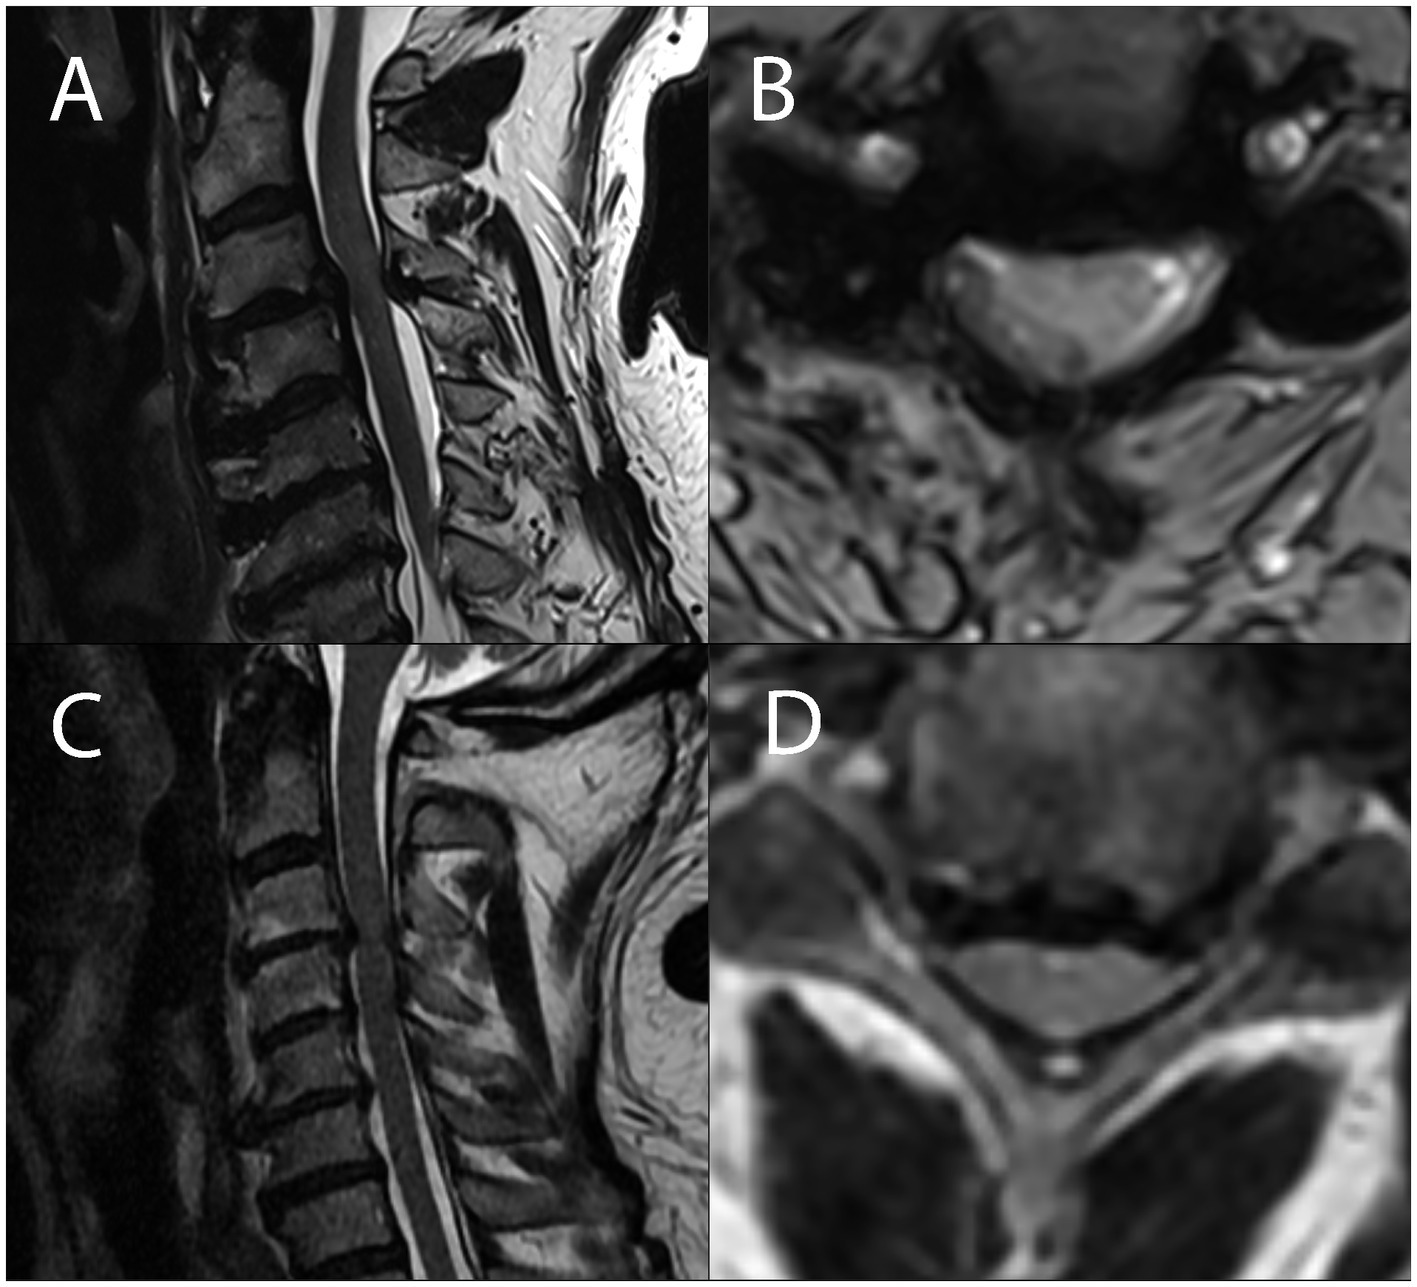

Figure 2

Sagittal and axial MRI sections of the cervical spinal cord showing degenerative compression in a patient with symptomatic degenerative cervical myelopathy (A,B) and in a patient without any myelopathic signs and symptoms (C,D), showing no visible difference in the severity of compression between DCM and ADCC subjects.